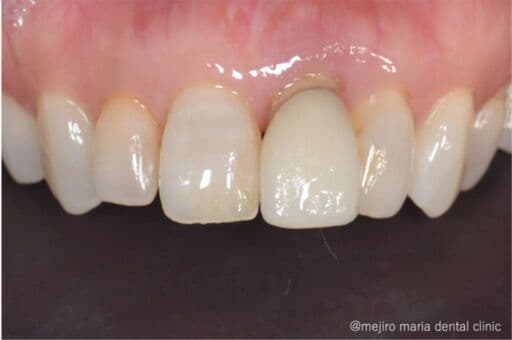

ブリッジの症例

結合組織移植術(CTG)により機能および見た目を改善

前歯のブリッジの見た目の問題と、食べ物が詰まるという2点を主訴に受診された方に、歯肉のボリュームをUPし、機能的、審美的に良好なブリッジ治療を完了した症例です。

before

after

治療内容 結合組織移植術(CTG)

治療期間 6ヶ月(外科処置から最終補綴物が入るまで)

治療回数 1回(他、抜糸、経過観察等を除く)

治療費用 165,000円〜(税込)

症例から言えること

本症例では、既存のブリッジが歯肉の大きな陥凹に合わせて作られていたため、見た目の不調和や清掃性の低下が生じていました。そこで、欠損部の歯肉ボリュームを回復させるために結合組織移植術(CTG)を行い、生理的な歯肉形態へと整えた後、新たに適合の良いブリッジを作製しました。歯肉形態を正しく整えることで、審美性・機能性の両面で質の高いブリッジ治療が実現できることを示した症例です。